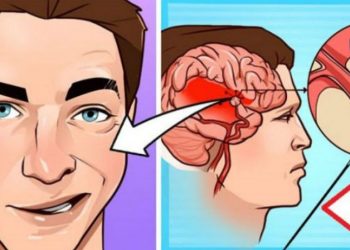

Lexo më shumëDetailsShtohen rastet e goditjeve në tru, mjekët tregojnë se si mund t’i shpëtoni jetën një personi

Nëse ataku kardiak jep shenja paralajmëruese, madje edhe një muaj përpara se të ndodhë, goditjet në tru ndodhin në çast...